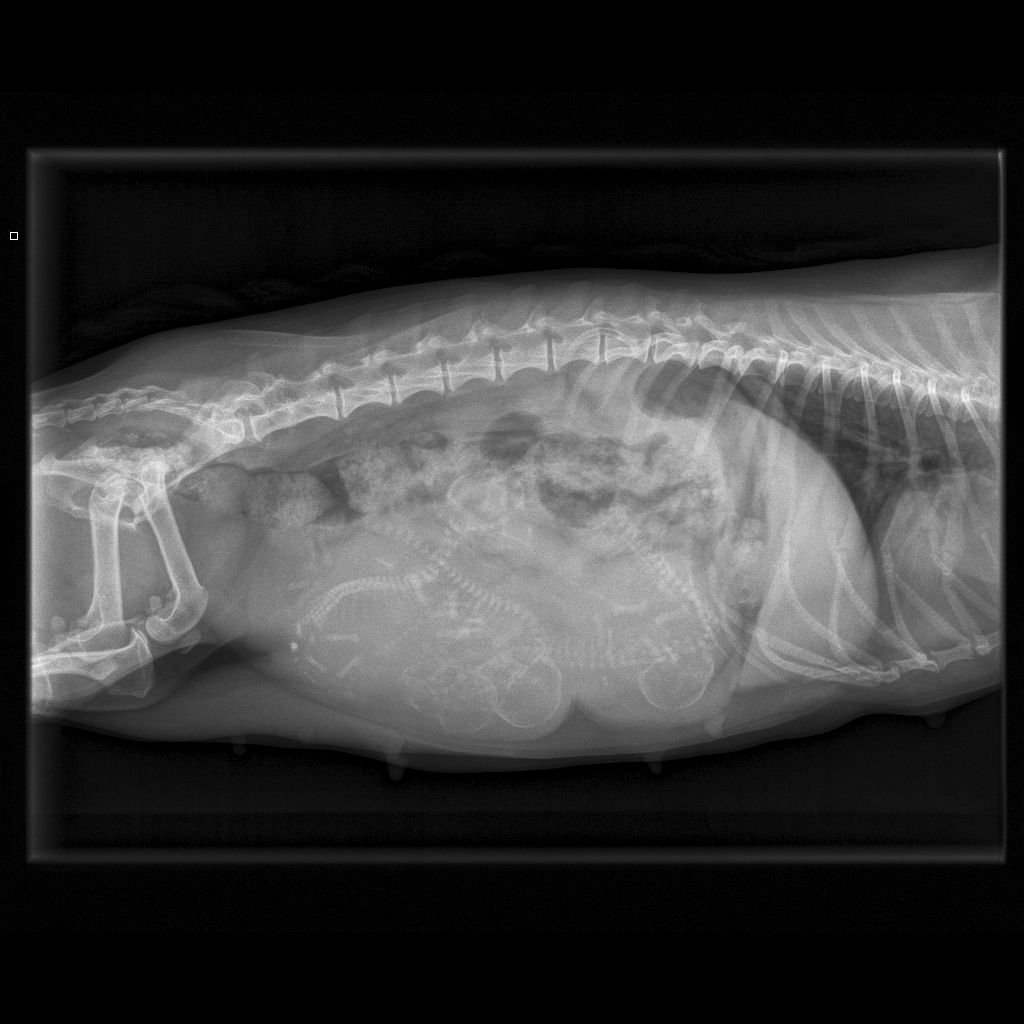

4/13/18 - Xrayed Caper today - she has 4 puppies in there!!! She is due in the next few days - send good thoughts! Scroll down to see her pregnancy picture.